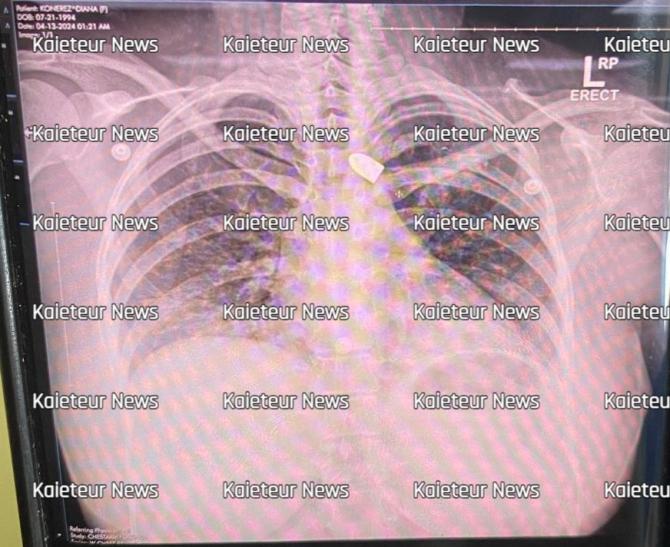

Alves was found shot deadabackofDiamond,East Bank Demerara (EBD) on the morning of Sunday July 7. Afewdaysafterthenews of her murder made headlines, Danello came forward publicly with her story. Danello had said that she could have suffered the same fate during a rainy nightonApril10afterataxi driverbasedatapopularcity hotel allegedly kidnapped, robbed, shot and left her for dead aback of Diamond too. The bullet from that night’s incidentisstilllodgedinher body Anx-rayshowedthatit is in a region close to her spine.